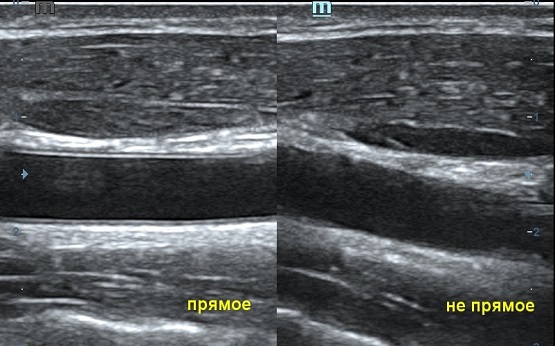

Ультразвуковая волна распространяется от пьезокристалла в направлении плоскости сканирования. Если волна отражается от поверхности исследуемой структуры под прямым углом и возвращается к пьезокристаллу напрямую, на сонограмме появляется четкая дифференцировка структуры и подчеркнутые контуры. Прямое отражение - самый важный критерий техники сканирования для измерения точных размеров органа. В случае отражения волны не под прямым углом эхогенность структуры меняется, дифференцировка на слои падает, контуры становятся нечеткими. Таким образом косой срез дает огромную погрешность измерения и затрудняет описание эхоструктуры объекта.

Как достичь прямого отражения Достаточно расположить объект на экране горизонтально, с помощью наклона датчика, чтобы волна отражалась от поверхности под прямым углом. При любом типе исследования любого органа или системы прямое отражение – залог достоверных результатов.